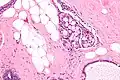

| Micrograph of collagenous spherulosis with the characteristic histomorphology - intratubular eosinophilic material with a spoke-like arrangement. H&E stain. | |

Collagenous spherulosis is characterized by a tubular/cribriform architecture with intratubular eosinophilic material that classically is arranged like the spokes of a wheel ("radial spikes"). There is usually no mitotic activity, and two cells populations (epithelial & myoepithelial) are present, like in benign breast glands.

The lesions are typically small (less than 50 spherules per lesion, less than 100 micrometers in size) and may be multifocal.